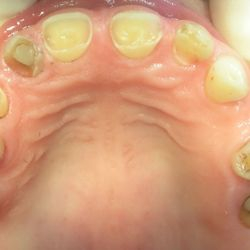

Η ασθενής της φωτογραφίας (65 ετών) προσήλθε στο ιατρείο παραπονούμενη για δυσκολία στη μάσηση. Ηταν επίσης δυσαρεστημένη με την όψη που είχαν τα φυσικά της δόντια.

Είχε επί χρόνια παραμελήσει την στοματική της υγεία με αποτέλεσμα πολλαπλές εξαγωγές των πίσω δοντιών της και φθορά των μπροστινών.

Το στόμα της αποκαταστάθηκε με μεταλλοκεραμικές στεφάνες και γέφυρες στα άνω δόντια και στα κάτω πρόσθια, ενώ στην κάτω γνάθο τοποθετήθηκε επίσης μια μερική οδοντοστοιχεία με άγκιστρα.

Μετά το πέρας της θεραπείας, η όψη του στόματος είχε βελτιωθεί δραματικά και η ίδια ανέφερε οτι πλέον μπορούσε να μασήσει όλες τις τροφές χωρίς περιορισμούς.